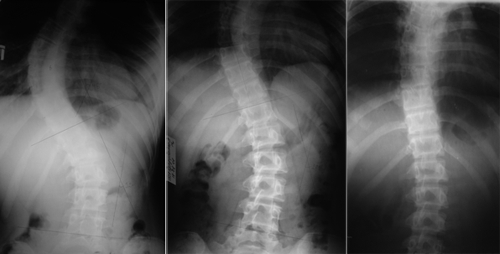

Врожденная форма данного заболевания встречается редко. Для диагностики смещения осевой части позвоночника используют рентгенографию. Снимки помогают составить предварительное заключение о степени выраженности заболевания.

Призывник обязан предоставить в военкомат рентгеновские снимки позвоночного столба, выполненные в двух проекциях — стоя и лежа. Врач устанавливает диагноз, опираясь на статью 66 Расписания болезней, а также на пункты а, б, в.

Деформация второй степени проявляется заметными изменениями в телах позвонков, и восстановить их нормальную форму уже невозможно. Лопатки и плечи пациента располагаются ассиметрично, а угол отклонения превышает 25°.

Деформация позвоночника нарушает его нормальную работу. Согласно пункту 66 Расписания болезней, врач может выдать освобождение от призыва, если у пациента диагностирован фиксированный сколиоз второй степени с углом искривления от 11 до 17 градусов.

При длительном течении заболевания пациент может испытывать симптомы статических нарушений, которые проявляются спустя 6 часов нахождения в вертикальном положении. В таких случаях врач фиксирует двигательные расстройства, изменения в сухожильных рефлексах и снижение мышечной силы. Пациенту становится сложно выполнять наклоны вперед и назад. Фиксированная деформация сохраняется даже при лежании на твердой поверхности. Визуально можно определить искривление позвоночника второй степени.

Избыточный вес иногда затрудняет выявление признаков фиксированного искривления из-за толстого слоя подкожно-жировой клетчатки. Юноша подлежит комиссованию, если у него обнаружено S-образное фиксированное левостороннее искривление поясничного отдела с ротацией влево на уровне L1–L4. Также у пациента отмечается снижение высоты межпозвоночных дисков.

Кандидат, собирающийся служить в армии, должен подтвердить наличие нарушений функций пораженного органа с помощью рентгеновских снимков и медицинского заключения врача.